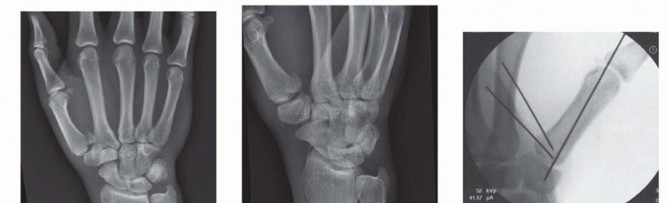

Our imaging protocol must be exhaustive to provide a three-dimensional understanding of the fracture morphology. Standard hand radiographs are insufficient due to the unique 30-degree pronated position of the thumb relative to the rest of the carpus. A True AP View of the Thumb CMC Joint (Robert's view) is obtained with maximal forearm pronation, placing the dorsum of the thumb flat on the cassette. This optimizes visualization of the joint space and the critical ulnar fragment. The True Lateral View (Billing and Gedda) is achieved with the hand pronated 20 degrees and the thumb flat on the cassette, with the X-ray beam tilted 10 degrees from vertical in a distal-to-proximal direction.

Image

For complex, multi-fragmentary Rolando fractures, a Traction View under fluoroscopy is indispensable. Distraction at the CMC joint utilizes ligamentotaxis to help delineate comminuted fragments and assess the potential for closed reduction and percutaneous pinning versus the absolute need for open plating. Furthermore, when plain films inadequately delineate the spatial orientation of fracture fragments, particularly in Zone 2, a high-resolution Computed Tomography (CT) scan is strictly indicated. 3D reconstructions are invaluable for preoperative templating, allowing the surgeon to precisely map screw trajectories and select appropriate plate morphology before entering the operating theater.